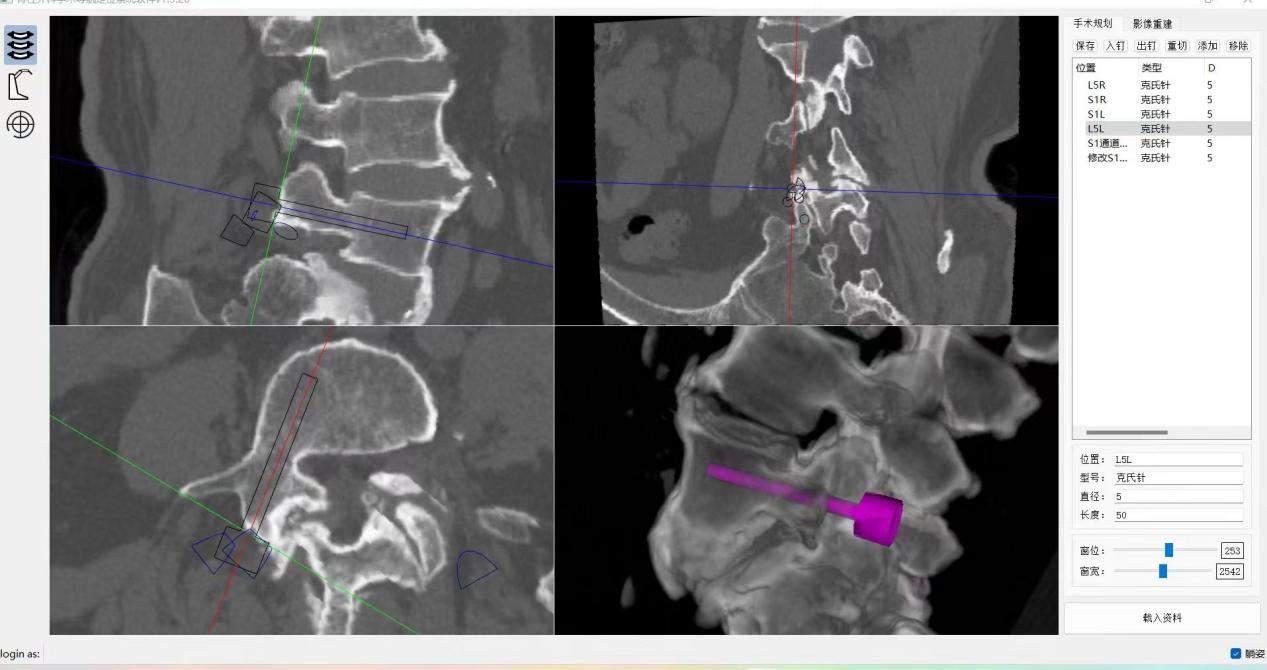

ORTHBOT脊柱机器人术前设计及术中穿刺

患者64岁,因间断性腰痛30年,加重伴间隙性跛行2年,辗转北京及西安多所医院,均建议采取传统外科开放手术治疗,患者因担心手术风险,迟迟不愿手术。经多方打听,患者慕名找到李全义主任医师。入院后李全义主任医师仔细研究患者的疾病特点,经过充分的沟通,决定采用目前骨科先进的微创、精准技术—机器人辅助微创手术。李全义主任医师团队顺利为患者实施ORTHBOT脊柱机器人辅助镜下腰5椎体滑脱复位椎管减压椎间融合内固定术,以机器人辅助微创手术解决了患者的痛苦,减少手术创伤及并发症,缩短手术时间。手术利用术前患者的影像学资料,模拟建立穿刺路径及各项参数,极大地优化手术方案使其更加精准、安全、有效,显著降低了制钉过程中神经根损伤的风险。